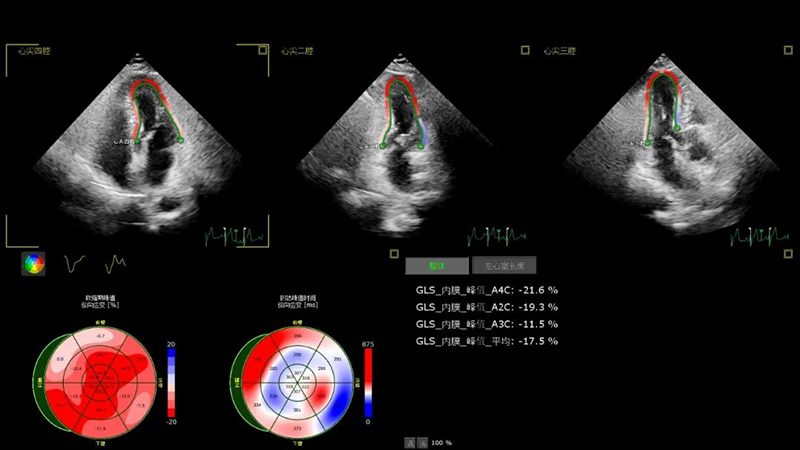

異常的左室心肌應(yīng)變圖